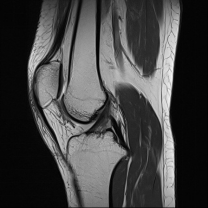

A torn ACL can be diagnosed by an orthopaedic specialist through: